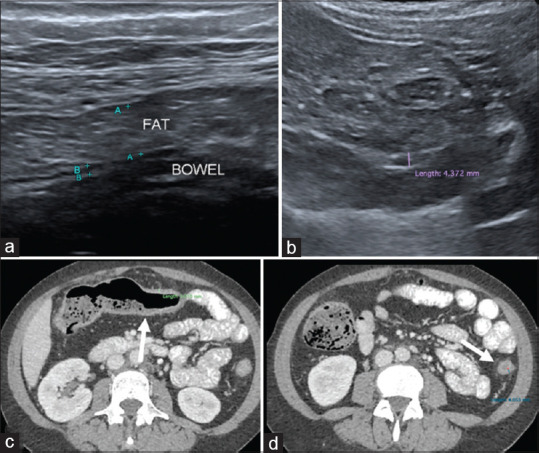

Methods: This is a prospective cross-sectional study of IUS performed on IBD patients in a tertiary centre. IUS parameters including intestinal wall thickness, loss of wall stratification, mesenteric fibrofatty proliferation, and increased vascularity were compared with endoscopic and clinical activity indices.

Results: Among the 51 patients, 58.8% were male, with a mean age of 41 years. Fifty-seven percent had underlying ulcerative colitis with mean disease duration of 8.4 years. Against ileocolonoscopy, IUS had a sensitivity of 67% (95% confidence interval (CI): 41-86) for detecting endoscopically active disease. It had high specificity of 97% (95% CI: 82-99) with positive and negative predictive values of 92% and 84%, respectively. Against clinical activity index, IUS had a sensitivity of 70% (95% CI: 35-92) and specificity of 85% (95% CI: 70-94) for detecting moderate to severe disease. Among individual IUS parameters, presence of bowel wall thickening (>3 mm) had the highest sensitivity (72%) for detecting endoscopically active disease. For per-bowel segment analysis, IUS (bowel wall thickening) was able to achieve 100% sensitivity and 95% specificity when examining the transverse colon.